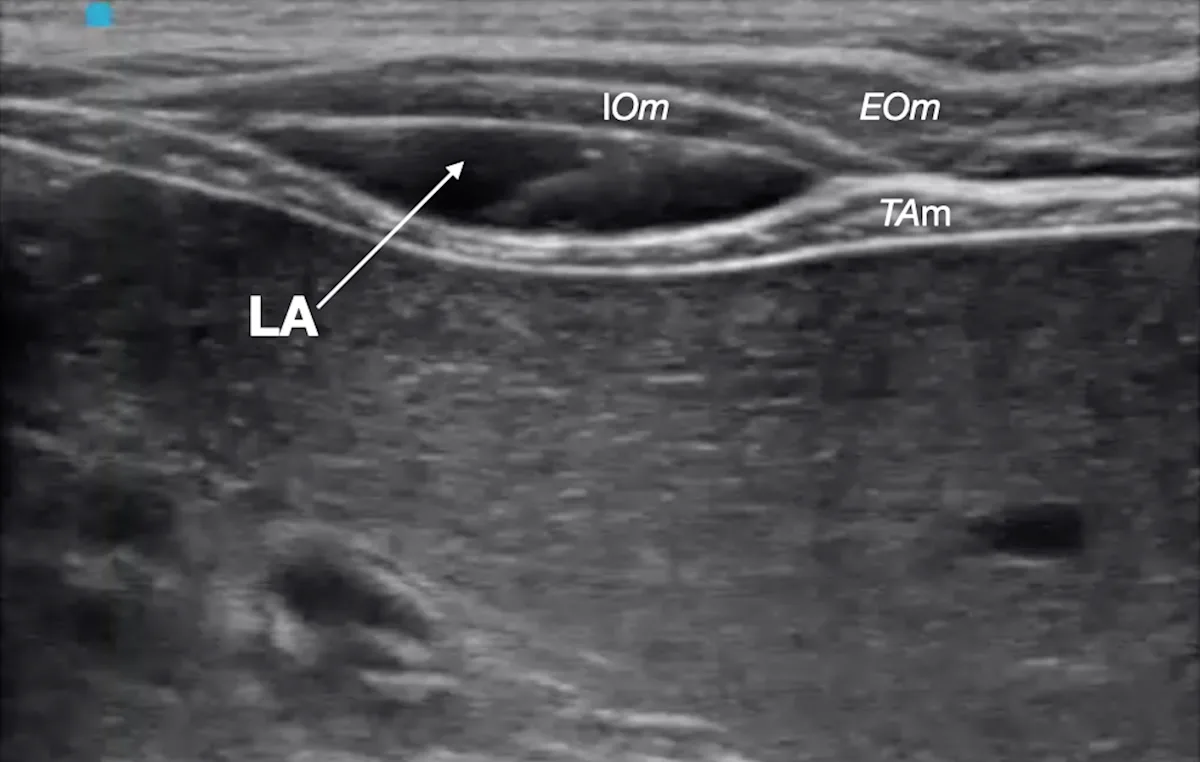

Step 12: Position the Transducer for Midabdomen Block

Slide the transducer caudally and slightly dorsally, approximately to the midpoint between the last rib and the iliac crest. Slide the transducer further laterally until the 3 layers of the abdominal wall can be seen in the acoustic window.

Author Insight

The transducer can be oriented transversally or parallel (longitudinal) to the midline. As the transducer is moved laterally, the rectus abdominis muscle disappears from the acoustic window, and only the transversus abdominis and external oblique muscles are visible. The aponeurosis of the internal oblique muscle is interposed between the transversus abdominis and external oblique muscles.

Step 13: Identify the Target Plane

Identify the target fascial plane (ie, TAP) as a hyperechoic line between the transversus abdominis muscle (TAm) and internal oblique muscle (IOm).

EOm, external oblique muscle; PP, parietal peritoneum

Step 14: Place the Needle for Midabdomen Block

With the transducer oriented parallel to the midline, introduce the spinal needle in-plane, and direct it to the fascial plane formed between the transversus abdominis and internal oblique muscles.

Step 15: Confirm Needle Placement

Rule out intravascular needle placement via negative aspiration test, and inject a small aliquot of the local anesthetic to confirm hydrodissection of the target fascial plane.

Step 16: Inject Local Anesthetic for Midabdomen Block

Inject one aliquot (0.3 mL/kg) of the total calculated volume of the local anesthetic (LA). Remove the spinal needle following injection.

IOm, internal oblique muscle; EOm, external oblique muscle; TAm, transversus abdominis muscle

Gentle advancement of the needle into the target fascial plane during injection helps promote wider spread of the local anesthetic.